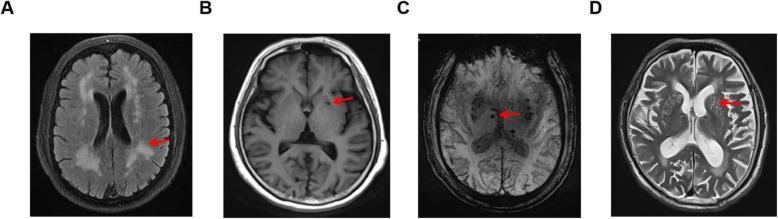

Consecutive first-ever stroke patients (n = 546) from the Affiliated Jiangning Hospital of Nanjing Medical University were enrolled. A total of 388 patients were enrolled according to minor cerebrovascular events definition (National Institutes of Health Stroke Scale Score ≤ 3) and exclusion criteria. MRI scans were performed within 7 days of stroke onset, and then neuroimaging markers of SVD including WMH, lacunes, cerebral microbleeds (CMB), and perivascular spaces (PVS), SVD burden scores were assessed. We completed baseline characteristics and evaluated the relationships of short-term outcomes to SVD neuroimaging markers and SVD scores. The 90-day modified Rankin Scale (mRS) was thought as primary outcome and was dichotomized as good functional outcome (mRS 0-1) and poor outcome (mRS 2-6). Secondary outcomes were stroke progression and stroke recurrence.

连续纳入南京医科大学附属江宁医院的首次卒中患者(n=546)。根据小血管事件的定义(NIHSS 评分≤3)和排除标准,共纳入 388 例患者。MRI 扫描在卒中发病后 7 天内进行,并评估 SVD 神经影像学标志物,包括脑白质病变(WMH)、腔隙、脑微出血(CMB)和血管周围间隙(PVS)、SVD 负荷评分。我们完成了基线特征,并评估了 SVD 神经影像学标志物和 SVD 评分与短期结局的关系。90 天改良 Rankin 量表(mRS)作为主要结局,分为良好功能结局(mRS 0-1)和不良结局(mRS 2-6)。次要结局为卒中进展和卒中复发。